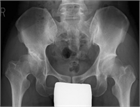

1. 異なる病態の多くの疾患が跛行の原因となり得る。

1. 歩行の観察から原因となる疾患を想定し、適切な検査を行う。